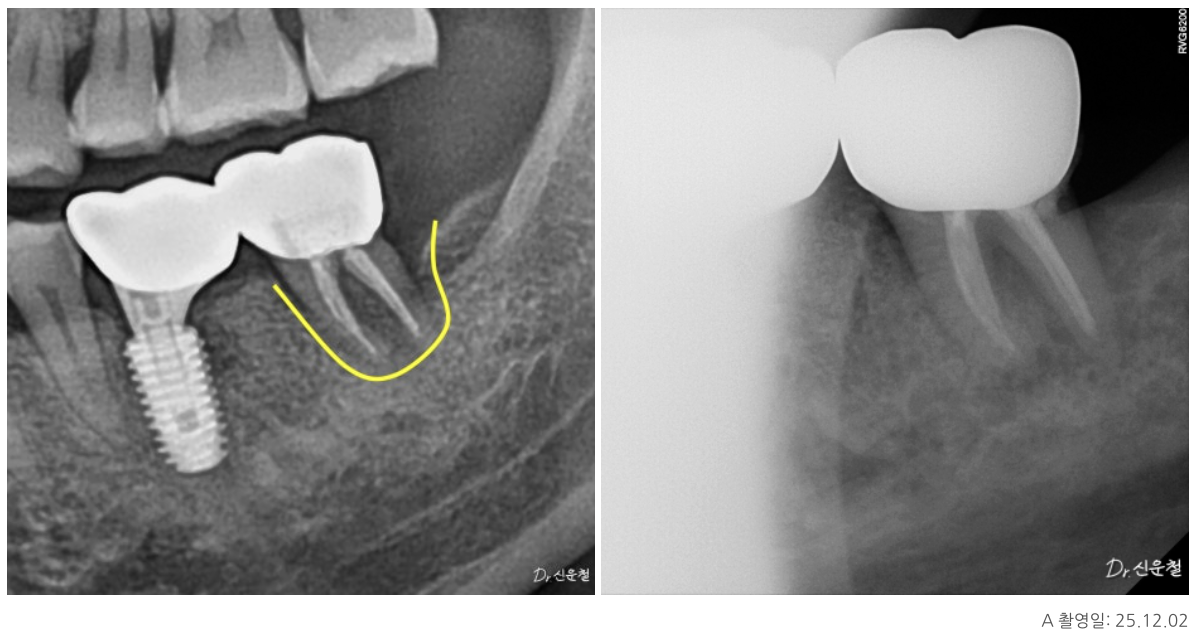

이 치아의 특징은 치아 안쪽 신경이 지나가는 길이

오랜 시간에 걸쳐 점점 막혀 있던 상태,

즉 석회화였습니다.

석회화란

원래 신경이 지나가야 할 공간이

시간이 지나면서 막히는 현상입니다.

방사선 사진에서 신경관이 잘 보이지 않거나

CT에서 신경이 있어야 할 자리가

빈 공간이 아닌 뼈처럼 보이는 경우가 이에 해당합니다.

겉으로 보면

“이제는 방법이 없는 치아”처럼 보일 수 있습니다.